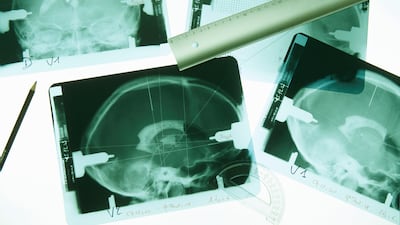

Dostoyevsky considered it a route for transcendence, Emily Dickinson obliquely made references in her poetry to 'It', Edward Lear called it 'the Demon' and it made Graham Greene contemplate suicide. The baffling medical phenomena we now know as epilepsy is derived from a Greek word, meaning "to seize upon" or "to attack". Not only has this led to the condition being stigmatised and linked to religious mysticism, it has intrigued physicians and historians since ages.

The history of epilepsy vacillates between it being perceived as a neurological disorder and the manifestation of the Divine. Grant utilises his rational scientific approach to investigate the condition medically but also, time and again, returns to the enigma of it. Since this is one of those disorders about which science is still inconclusive, veering between the two extremes makes sense.

Grant traces the treatment of epilepsy, which in the past included the absurd practices of bloodletting and prescribing high dosages of bromide. Even now, most medication prescribed only succeeds in "managing" seizures, not in curing epilepsy. The title of the book refers to the olfactory hallucination associated with temporal lobe epilepsy, which in simple terms is called an aura. Many epileptic patients report a peculiar sense of burning rubber moments before they have a seizure.